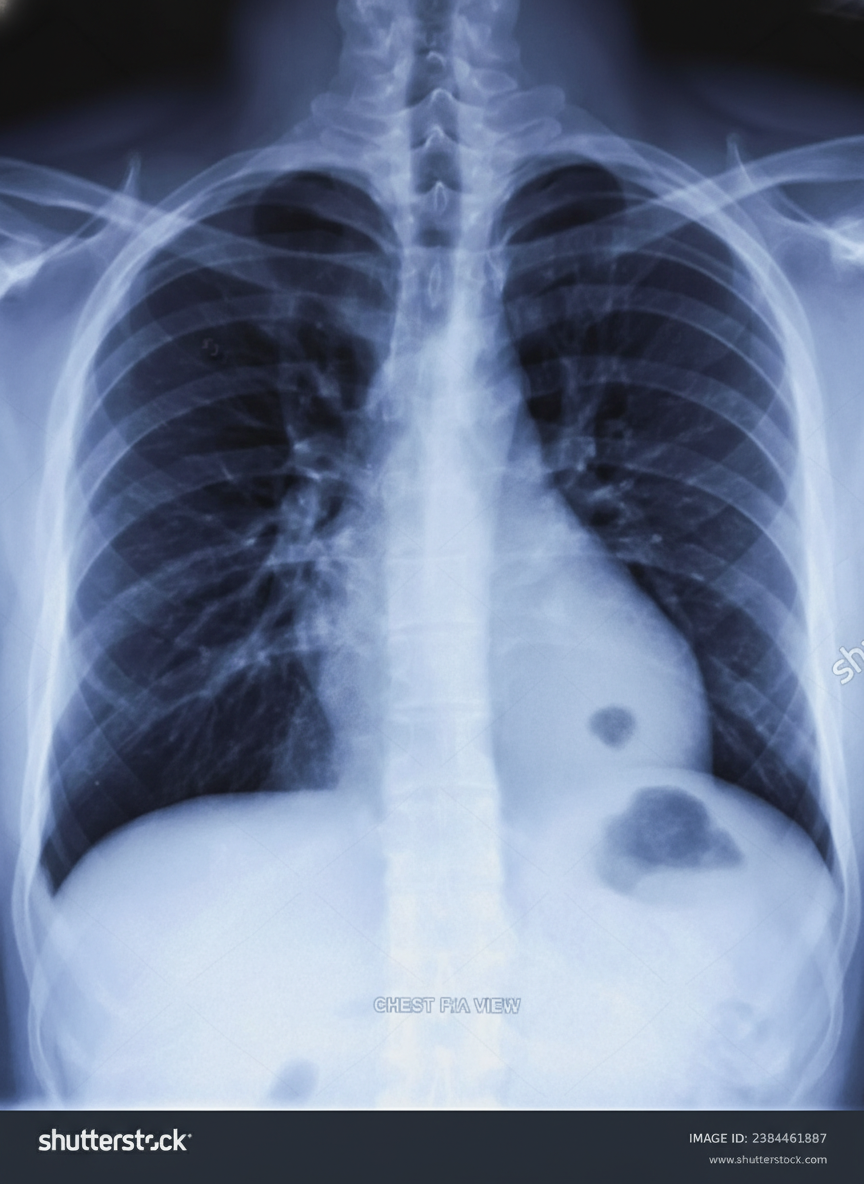

A 45-year-old man presents for a follow-up visit as part of his immigration requirements into the United States. Earlier this week, he was administered the Mantoux tuberculin skin test (TST). Today’s reading, 3 days after being administered the test, he shows an induration of 10 mm. Given his recent immigration from a country with a high prevalence of tuberculosis, he is requested to obtain a radiograph of the chest, which is shown in the image. Which of the following is true regarding this patient’s chest radiograph (CXR)?